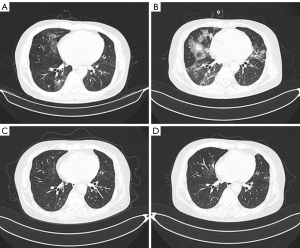

A 70-year-old man was enrolled in a clinical trial of anti-CD19 CAR T-cell therapy (ChiCTR1800019622) as a refractory FL patient at our center in November 2023. He was first diagnosed with COVID-19 when he was evaluated as having a CR in January 2024, without receiving a vaccine against SARS-CoV-2. He had symptoms of fever, cough, and breathlessness and had an oxygen saturation of 90–93% without oxygen inhalation. SARS-CoV-2 was found to be positive, while the CRP was 75.3 mg/L and the IL-6 level was 301 pg/mL. The expression of CD19 in B lymphocytes in the peripheral blood was 0.06%, and hypogammaglobulinemia was 15.1 g/L at this time. CT indicated interstitial pneumonia in both lungs (Figure 2A). He received molnupiravir, methylprednisolone (60 mg daily for 14 days), and symptomatic treatment, but his symptoms were not relieved, and SARS-CoV-2 remained positive. In the following 2 months, he received Paxlovid, methylprednisolone (40–60 mg, daily), and continuous oxygen therapy; however, he had persistent hypoxemia, severe cough, and persistent positive SARS-CoV-2 test results.

In March 2024, he was hospitalized again because of severe hypoxemia with a cough and an oxygen saturation of 86–99% without oxygen inhalation. The CRP was 58.3 mg/L and IL-6 was 275 pg/mL, respectively, and the SARS-CoV-2 remained positive. His interstitial pneumonia worsened, with ground-glass shadows in his left lung (Figure 2B). He was diagnosed with long COVID: ongoing symptomatic COVID-19 (4–12 weeks after infection) (10). Bronchoscopy revealed evidence of SARS-CoV-2 infection in alveolar lavage fluid. The patient received molnupiravir and methylprednisolone (160 mg daily for 3 days, followed by 80 mg daily for 7 days). However, his severe hypoxemia (oxygen saturation at 86–99% without oxygen inhalation) and cough did not resolve. The SARS-CoV-2 tested was positive at this time. The patient subsequently received ruxolitinib (5 mg, twice daily) in combination with a gradually reduced dose of methylprednisolone starting in March 2024. The CRP was 45.1 mg/L and IL-6 was 58 pg/mL at the beginning of salvage therapy. One month later, the oxygen saturation of the patient was about 91–93% without oxygen inhalation. Two months after salvage therapy with ruxolitinib, oxygen saturation returned to 95–97% without methylprednisolone. CT revealed significant absorption of interstitial pneumonia (Figure 2C,2D). His SARS-CoV-2 test results were negative, while the CRP was 10.5 mg/L and IL-6 was 8.2 pg/mL, respectively (Table 1). He did not develop any degree of hemocytopenia during ruxolitinib salvage therapy. The lymphoma was in a persistent CR state during multiple COVID-19 infections. In particular, the lymphoma remained in a continuous state of CR for approximately 10 months.